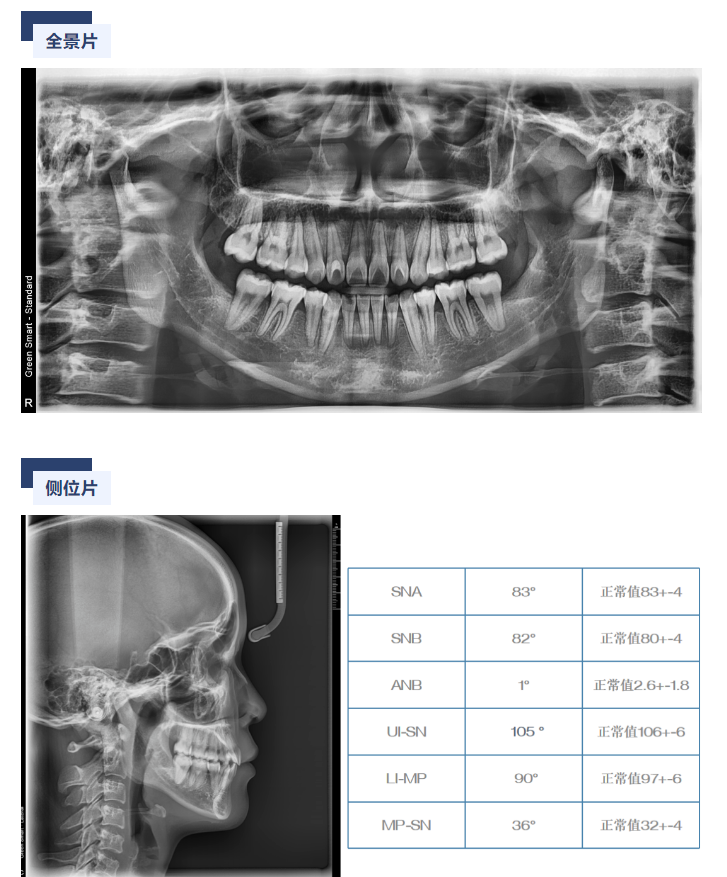

威派病例分享丨一例成人龅牙的矫治病例(李阳斌 )